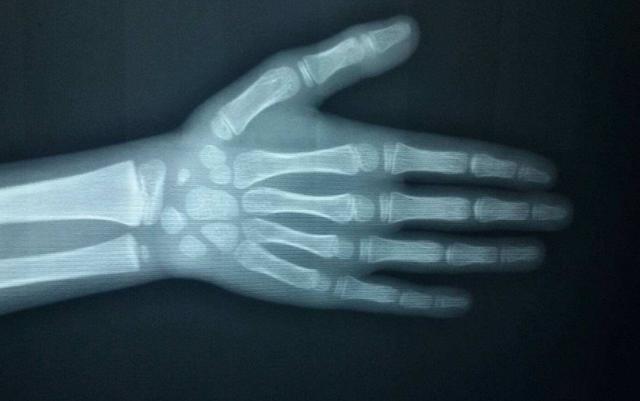

这里所说的16岁和14岁,并非指时间年龄,而是指“骨龄”,什么是骨龄?字面意思就是骨头的年龄,每个人都拥有两个年龄,一个叫时间年龄,就是今年你多大了、几岁了,一个是生理年龄,就是骨龄,而骨龄是衡量一个人还能长多高的标准之一。

那怎么知道自己的骨龄呢?很简单,有影像科的医院都可以拍骨龄片,拍完后拿给我们生长发育医生看就行,拍的时候取左手正位片(可以百度下)。